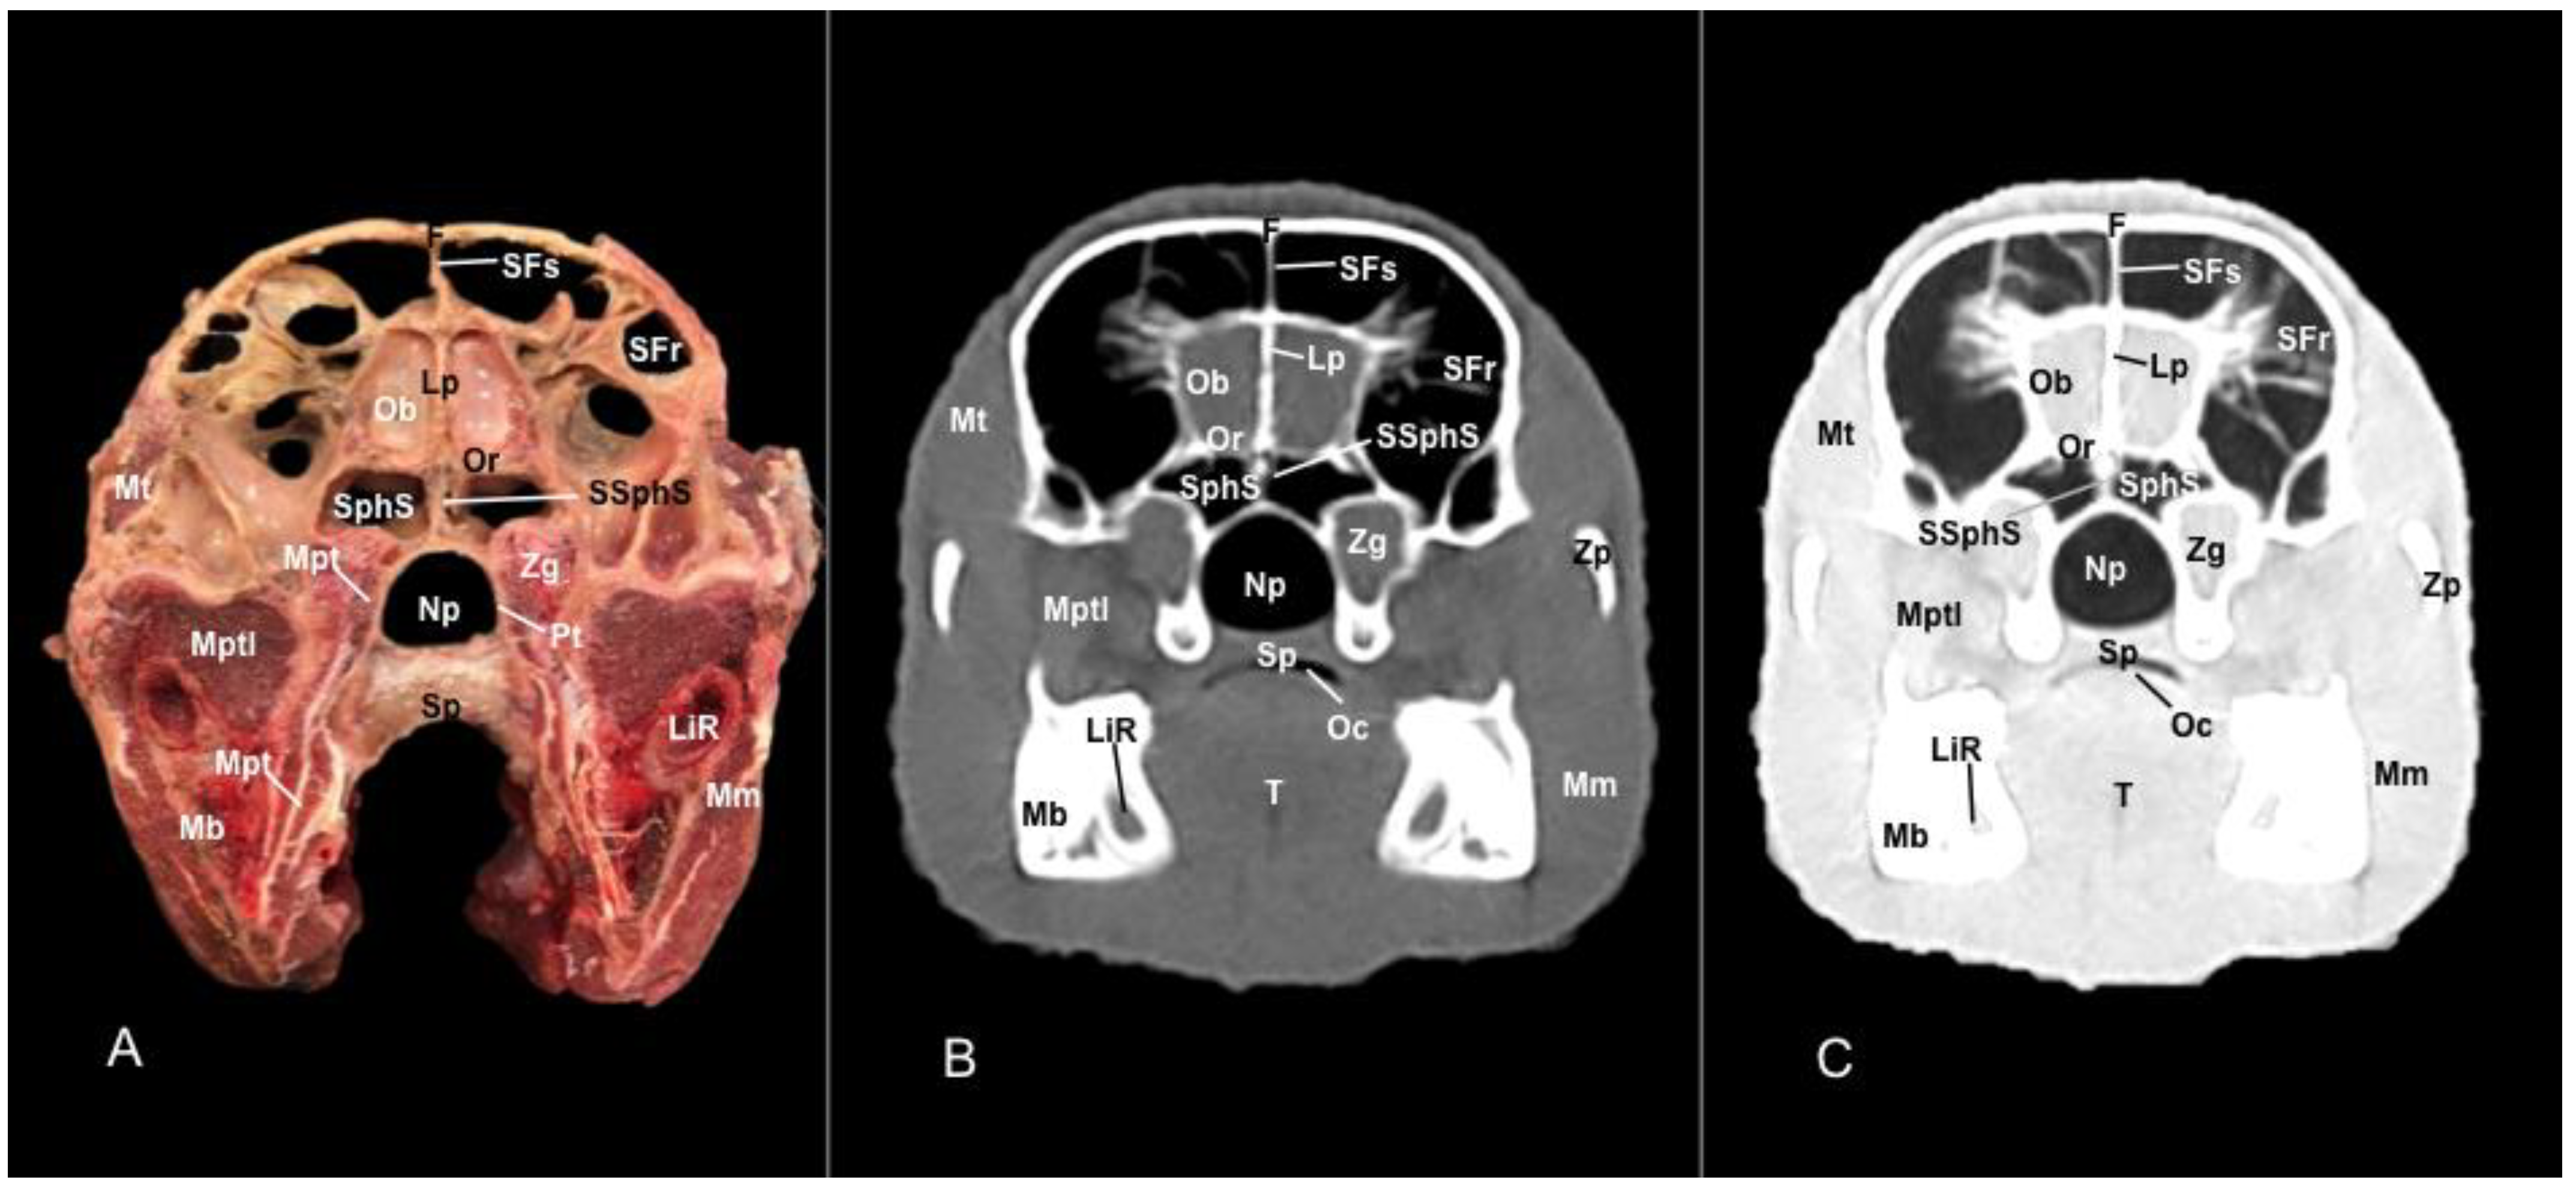

3.1. Anatomical Sections

3.2. Computed Tomography (CT)